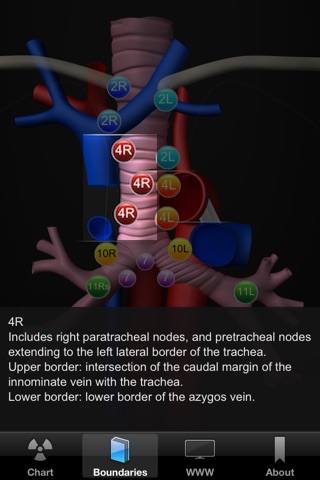

Transbronchial needle aspiration (TBNA) is an important technique for bronchoscopists. Although endobronchial ultrasound transbronchial needle aspiration (EBUS) is more sensitive overall, TBNA is still recommended for patients with bulky mediastinal lymphadenopathy. In addition TBNA is cheaper and faster than EBUS and can be performed during a normal flexible bronchoscopy. To master the art of TBNA extensive knowledge of the bronchial and mediastinal anatomy is required, as well as the necessary skills for adequate lymph node sampling. For novices it is especially difficult to determine the right location to sample a lymph node. The TBNA app is designed to familiarize you with a concept that is easy to apply and will help you to determine the right location in any patient. Central in the TBNA app is the mediastinal and hilar lymph node map. When tapping one of the lymph node stations a sequence of CT and bronchoscopy images is shown. This sequence of five images will take you from the CT scan to the actual bronchoscopy images step by step. A second tab boundaries shows you the boundaries of the lymph node stations on the map.